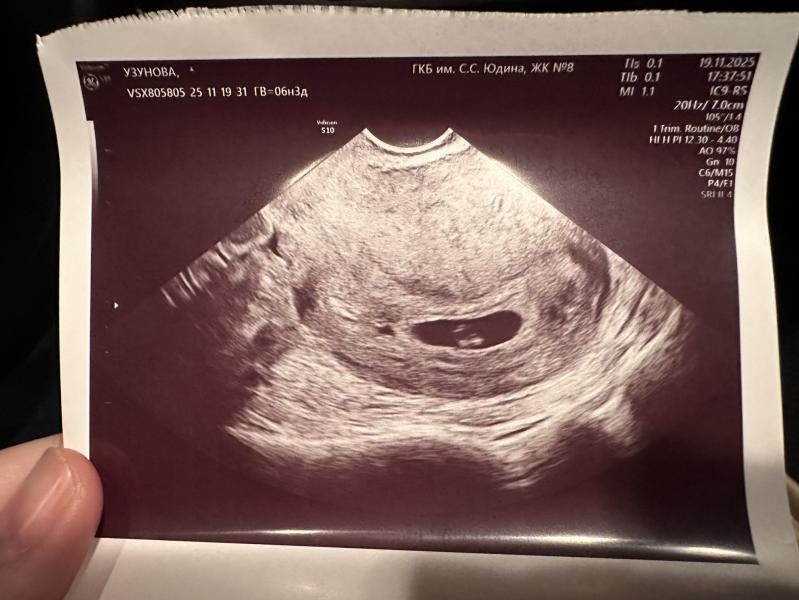

Выявлено плодное яйцо правильной формы, средний внутренний диаметр 15.0 мм

Соответствует 6 неделям 1 дню беременности.

Желточный мешок 1: определяется. Диаметр 4.1 мм.

Эмбрион/плод: определяется 1 эмбрион/плод.

Характеристики эмбриона/плода 1: копчико-теменной размер 3.9 мм, соответствует 6 неделям 1 дню беременности.

Сердцебиение: определяется, ЧСС 150 ударов в минуту.